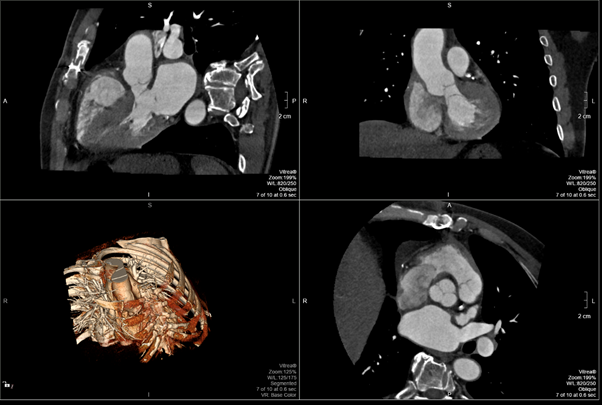

Six months after the operation, the patient is in functional class I according to NYHA, he has no complaints from the cardiovascular system. The patient underwent a cardiac MRI. There are no signs of infective endocarditis (Figure 2).

Figure 2 Cardiac MRI 12 months after surgery.